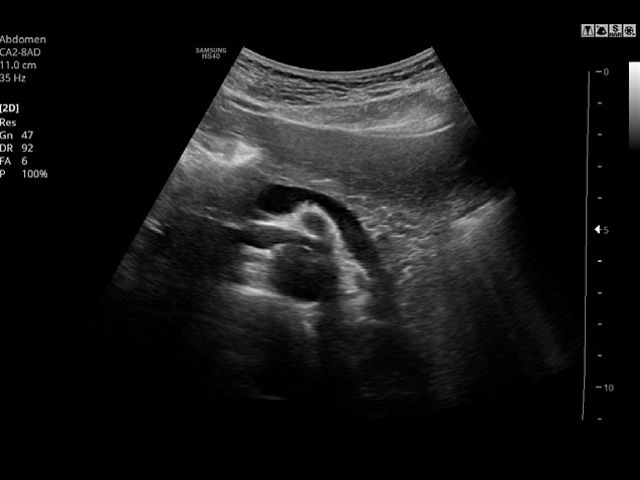

CA2-8ADApplication:Abdomen, Obstetrics, Gynecology, Pediatric, Musculoskeletal, Vascular, Urology, Emergency |